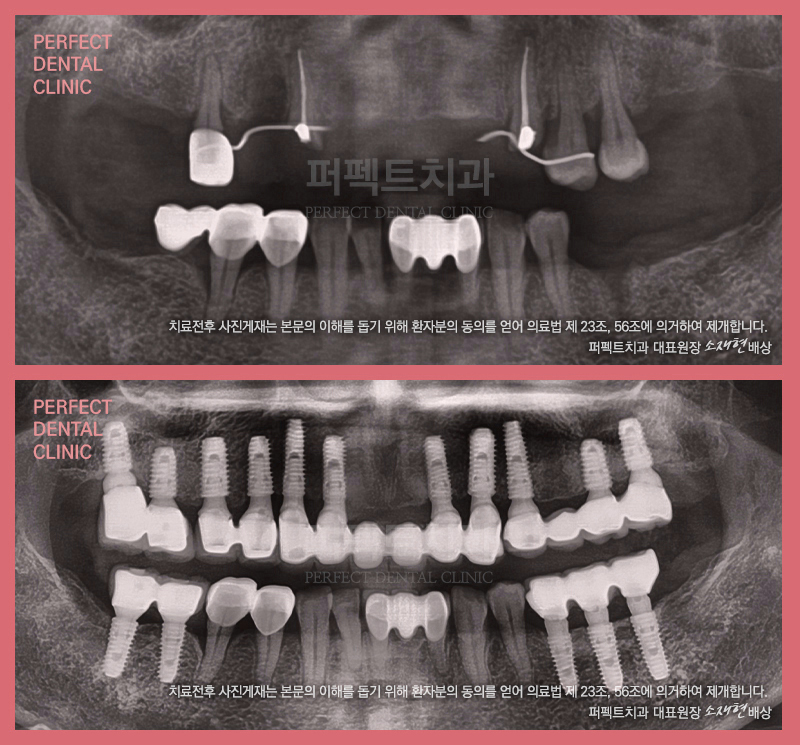

실제 퍼펙트치과에서 치료를 받으신

환자분들의 치료 전/후 사진은 물론